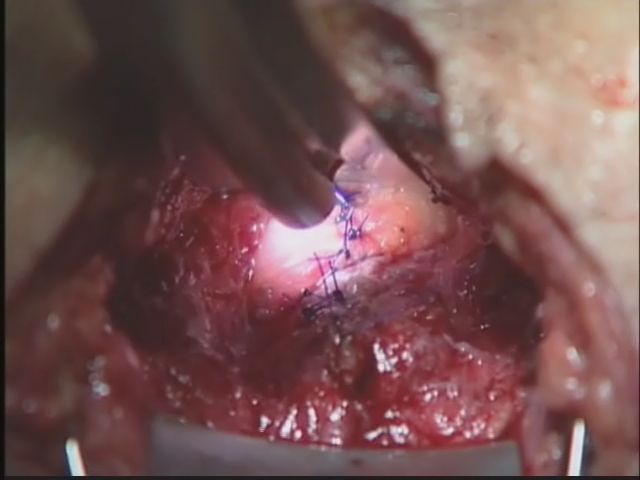

Transperineal Repair of Comp..

Transperineal Repair of Comp..

Mary Samplaski, MD; Hadley M. Wood, MD; Feza H. Remzi, MD / CINE-MED